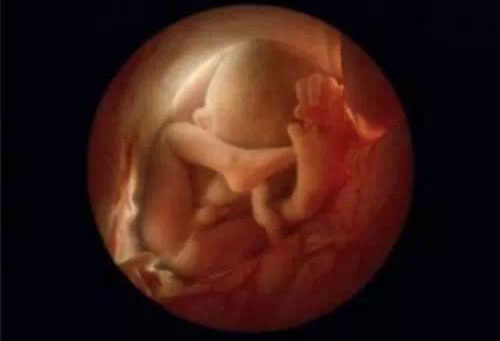

第9周,你的"新居民"有近2.5厘米长,重量还很轻,差不多有葡萄粒般大小,但身体的基本结构已经形成,体重将会快速增长。他看起来也越来越像个小人了,胚胎期的"尾巴"现在已经彻底消失,他的身体各部分的发育,如器官、肌肉和神经等都在步入正轨。

第10周,此时眼睑半闭,几周内会完全闭合

10周,胎儿已经可以使用双手来探索周围的环境

10周,现在就是通常所说的胎儿期 的开始,这段时期他体内的组织和器官快速生长成熟。他的重要器官——肝脏、肾、肠胃、大脑和肺都已经各就其位,并开始"工作"了,它们还会在你的整个孕期 中继续发育。他的肝脏继续制造着红血球。在这之前,卵黄囊一直负责向红血球提供养料,但现在它已经不再被需要,并开始消失。